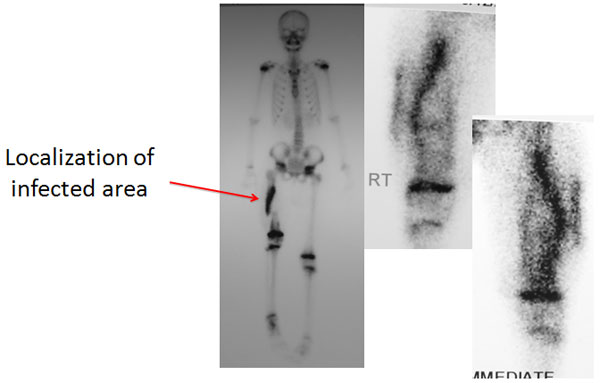

| Bone Scan |

| A bone scan was done which showed the area of infection. The entire shaft was infected on the inner posterior surface. |